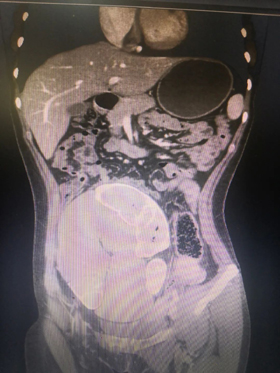

蔡轩主治医师接诊后,详细询问病史和查看以往检查结果后,考虑并非没有手术机会,即刻安排多项检查,准备仔细评估手术风险和治疗预后,希望能帮助小芳解决这个多年的顽疾。在完成结肠镜、腹部增强CT、窦道造影和盆腔MRI等多项检查后,毕敬涛副主任医师和赵景明主任医师立刻对此病例进行了联合会诊,最终考虑小芳的病症是消化道重复畸形所致。

腹腔内出现第二套消化道肠管

手术当天由毕敬涛副主任医师、赵景明主任医师和蔡轩主治医师主刀完成,术中探查发现患者存在第二腹腔,其表面可见被顶起的重复输尿管畸形,而腔内的重复肠管为类结肠结构并一直延续到盆底,子宫及附件结构已被挤压到了左侧盆壁。术中小心保护输尿管结构与周围重要血管和神经,充分游离重复肠管并在盆底处将其离断。关闭腹腔后再改变患者体位为侧卧位,沿处理臀部窦道,贯通至盆腔内。经过近数小时的艰苦奋战,按照既定计划,三位专家成功将完整的重复消化道移出腹腔!